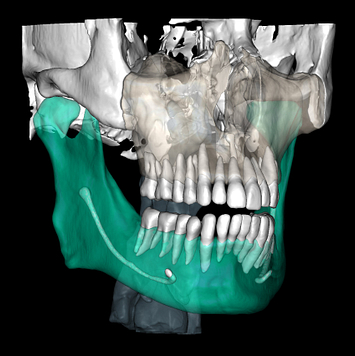

CBCT segmentation

This is one feature that actually made Diagnocat very popular early on. It was the only software that made CBCT segmentation easy. Nowadays, there are several different companies and software that carry out segmentation. Diagnocat was the first and is still arguably the best at it.

So what is Segmentation? It basically means taking the CBCT and delineating all the different 3D structures, bones, individual teeth, etc.

These can then be individually exported via the software by generating STL files from CBCT dicom data. This can be used in other dental software. Jaw STLs can be used in Modjaw (jaw motion capture) for TMJ analysis, for example. As well as in exocad to help visualize the jaws for surgical planning or guide creation.

Being able to take a DICOM file and turn it into STLs is useful for a host of different CAD/CAM indications.

- CBCT segmentation

STLs of upper and lower jaws imported into Modjaw for TMJ analysis in jaw motion. this is made possible by CBCT segmentation using Diagnocat.

The surgical crown lengthening guide was made with the aid of maxilla STL to visualize crestal bone level. Again thanks to CBCT segmentation by Diagnocat.

CBCT Segmentation into STL

Generate STL files from CBCT DICOM data.

Generate maxilla and mandible in one STL file or face, teeth, maxilla, mandible, airway, cranial base, canals as separate STL files.